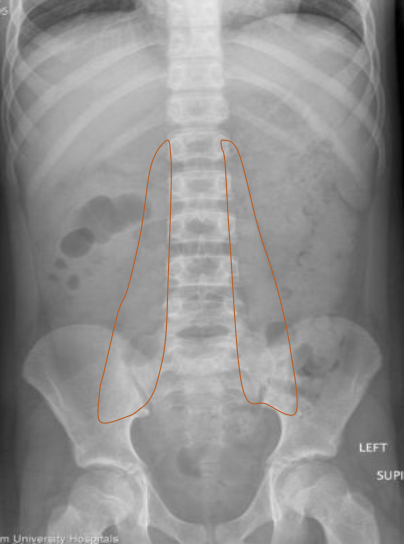

Psoas muscle

Standard projections for AXR?